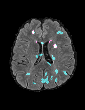

In recent years, data-driven machine learning (ML) methods have revolutionized the computer vision community by providing novel efficient solutions to many unsolved (medical) image analysis problems. However, due to the increasing privacy concerns and data fragmentation on many different sites, existing medical data are not fully utilized, thus limiting the potential of ML. Federated learning (FL) enables multiple parties to collaboratively train a ML model without exchanging local data. However, data heterogeneity (non-IID) among the distributed clients is yet a challenge. To this end, we propose a novel federated method, denoted Federated Disentanglement (FedDis), to disentangle the parameter space into shape and appearance, and only share the shape parameter with the clients. FedDis is based on the assumption that the anatomical structure in brain MRI images is similar across multiple institutions, and sharing the shape knowledge would be beneficial in anomaly detection. In this paper, we leverage healthy brain scans of 623 subjects from multiple sites with real data (OASIS, ADNI) in a privacy-preserving fashion to learn a model of normal anatomy, that allows to segment abnormal structures. We demonstrate a superior performance of FedDis on real pathological databases containing 109 subjects; two publicly available MS Lesions (MSLUB, MSISBI), and an in-house database with MS and Glioblastoma (MSI and GBI). FedDis achieved an average dice performance of 0.38, outperforming the state-of-the-art (SOTA) auto-encoder by 42% and the SOTA federated method by 11%. Further, we illustrate that FedDis learns a shape embedding that is orthogonal to the appearance and consistent under different intensity augmentations.